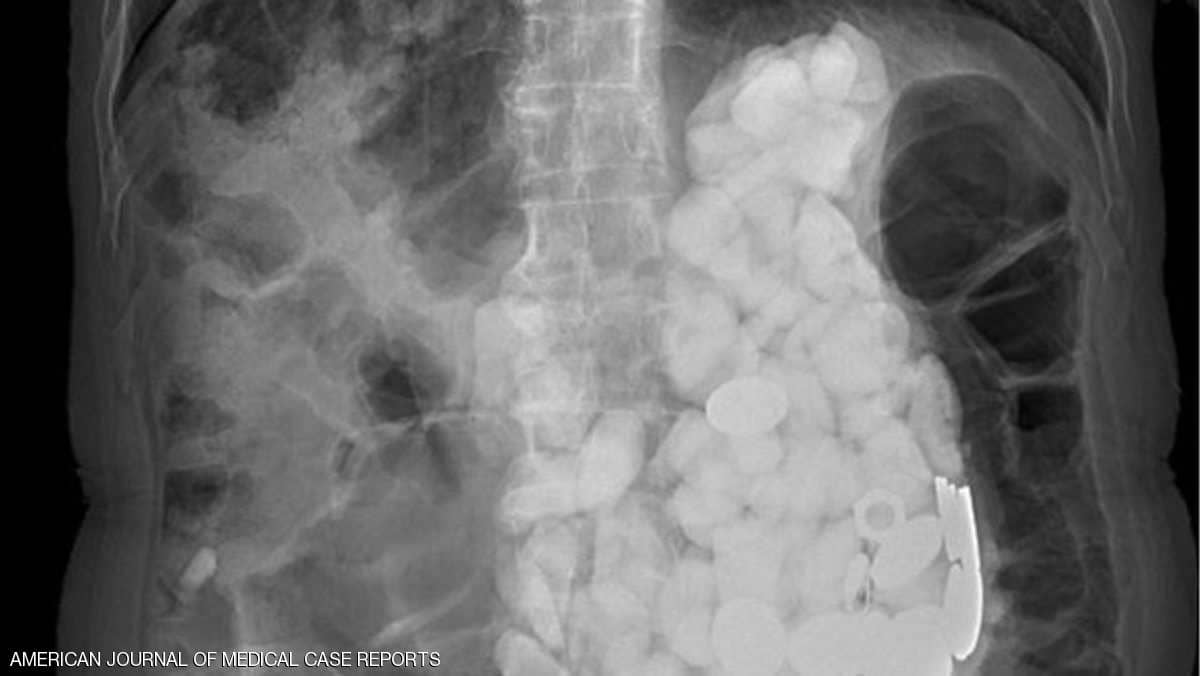

تفاجئ أطباء بعدما عثروا على مجموعة من الحجارة وأغطية زجاجات ونقود معدنية في معدة مريض، أجروا له عملية جراحية لإخراجها بعد أن تناولها أثناء تعرضه لنوبات قلق.

وأجرى أطباء بمستشفى Ilsan Paik بجامعة إنجي الكورية الجنوبية، مجموعة من الفحوصات لمعرفة السبب الكامن وراء هذه الأعراض، حيث شعروا بشيء يشبه الحجارة عند لمس بطنه، واكتشفوا تراكم أجسام في المعدة كلها يصل وزنها إلى كيلوغرامين.

ولم تفلح محاولات الأطباء في إخراج الأجسام من معدة الرجل الذي ولد بإعاقة ذهنية، باستخدام طريقة المنظار نظرا لكثرتها، مما دفعهم للحل الجراحي.